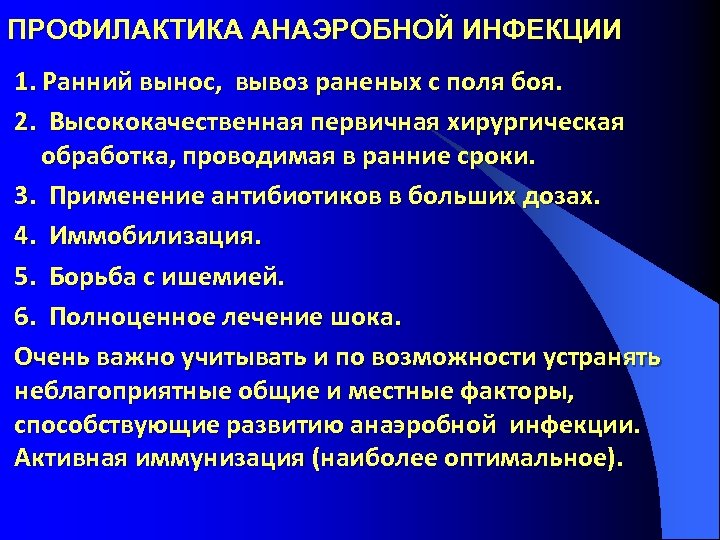

ПРОФИЛАКТИКА АНАЭРОБНОЙ ИНФЕКЦИИ 1. Ранний вынос, вывоз раненых с поля боя. 2. Высококачественная первичная хирургическая обработка, проводимая в ранние сроки. 3. Применение антибиотиков в больших дозах. 4. Иммобилизация. 5. Борьба с ишемией. 6. Полноценное лечение шока. Очень важно учитывать и по возможности устранять неблагоприятные общие и местные факторы, способствующие развитию анаэробной инфекции. Активная иммунизация (наиболее оптимальное).

ПРОФИЛАКТИКА АНАЭРОБНОЙ ИНФЕКЦИИ 1. Ранний вынос, вывоз раненых с поля боя. 2. Высококачественная первичная хирургическая обработка, проводимая в ранние сроки. 3. Применение антибиотиков в больших дозах. 4. Иммобилизация. 5. Борьба с ишемией. 6. Полноценное лечение шока. Очень важно учитывать и по возможности устранять неблагоприятные общие и местные факторы, способствующие развитию анаэробной инфекции. Активная иммунизация (наиболее оптимальное).